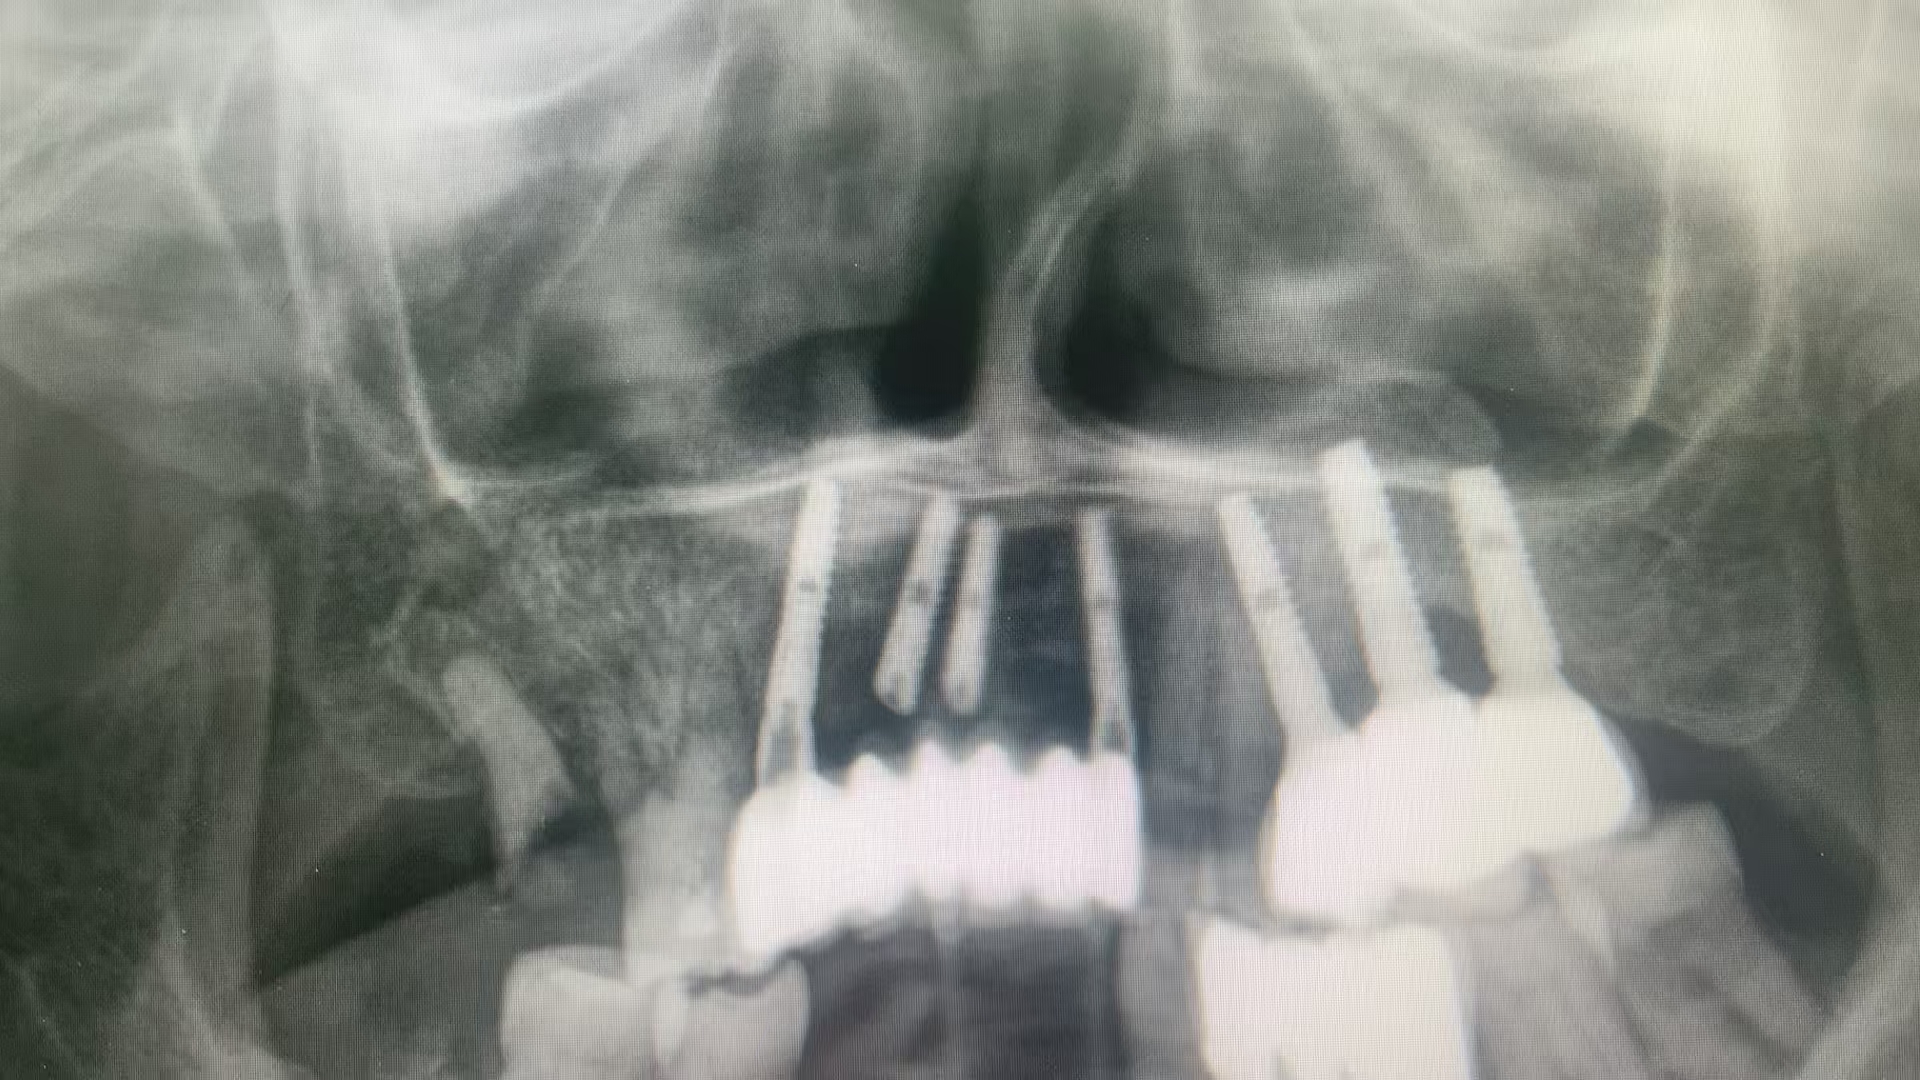

沉没修复,医者患者都沉默了

问题是解决了,可是,可是,还是沉默吧。

这是什么种植方法?